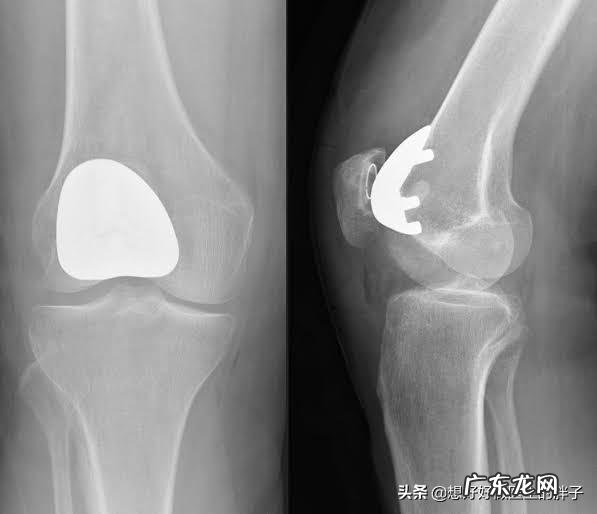

当病程进行到了晚期,患者关节间隙会越来越严重,关节也会随之出现明显的变形,有的老年人会出现明显的o型腿,或者是x型腿的改变,基本都是源自于关节内软骨的磨损,导致的关节畸形 。而患者呢,也会出现明显的关节疼痛,严重影响患者的生活质量,有一些患者会出现明显的夜间痛以及休息痛 。

针对骨关节炎的zhi疗,要有阶梯早期骨关节炎的zhi疗:早期骨关节炎的患者症状相对来讲比较轻,那么此时我们需要做的是建议老年患者减轻体重,减少长时间行走的量,一般建议老年人每天控制在行走6000步到8000步左右即可,最好是在游泳池中行走或者是游泳,这种对于关节没有负担的动作是非常好的运动方式 。也建议老年人进行关节肌肉的康复锻炼,促进肌肉的强化,保更好的保护关节 。在这个阶段一般不建议患者采取药物zhi疗的办法,如果疼痛比较明显,但是检查反而表现的不是很严重的话,建议可以采取外用非甾体镇痛药的办法来控制疼痛 。

中期骨关节炎的zhi疗:患者到了中期,关节疼痛会有明显的加重,在坚持早期骨关节zhi疗的基础上,可以建议患者口服一些非甾体镇痛药,通常我们建议口服西乐葆这一类比较对胃黏膜伤害较轻的药物来控制疼痛 。也可以采取一些物理zhi疗的办法,比如微波zhi疗,超声波zhi疗,帮助控制关节炎症的进展 。由于中期骨关节炎患者的关节软骨已经有了明显的退变,部分患者的关节软骨会出现明显的皲裂与脱落,破碎 。那么此时,建议给关节内进行关节腔注射玻璃酸钠的办法来增加关节软骨的弹性,减轻关节软骨的摩擦 。